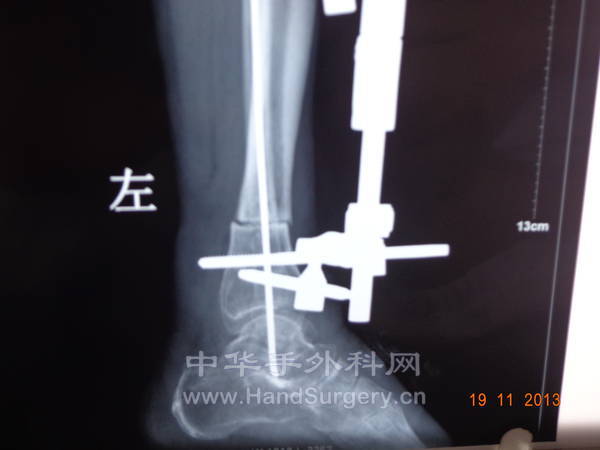

[断指再植] 小腿离断

今天终于来复查了。

什么时候换做外固定架

骨折咋固定的呀?能不能发X片呢?